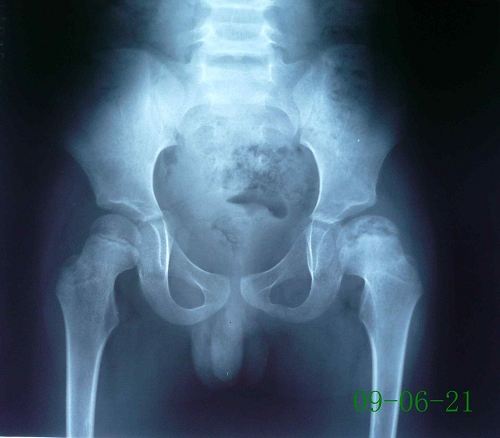

儿童股骨头坏死,又称股骨头骨骺软骨炎、股骨头无菌性坏死或扁平髋。是儿童常见的原因不明的软骨病,多发于2~12岁儿童,以退行性变或坏死开始,继后出现再生或重新钙化,最终出现股骨头的坏死。一开始表现为膝关节-髋关节痛,步行不便或跛行,患髋不能屈伸、内收。因为有的很隐匿,孩子只是有点疼,跛行两天,有像是没事了,只有磁共振才能发现股骨头的缺血水肿,本病早期诊断早期治疗十分重要,但又有几个家长愿意让孩子因为髋关节有点疼痛就去做磁共振呢?

非手术治疗:非手术治疗主要用于年龄<6岁,CatterallⅠ-Ⅱ型的患儿。方法有卧床休息、外展位牵引、石膏固定、外展支架或矫形器矫正等,这些支具需下肢外展40°-45°,内旋10°-15°或无内旋,以期获得包容,防止脱位。佩戴支具后髋、膝关节可自主活动,这不仅有利于股骨头形态的重塑和保持良好的活动范围,且能促进关节滑液的流动,有利于软骨和滑膜的营养。

手术治疗:手术治疗主要应用于年龄>6~8岁,Catterall II―III期以上、部分Ⅳ期的患儿以及髋关节半脱位、有临床危象征(髋关节疼痛、功能受限)的患儿。近年来随着对该病的进一步认识,多倾向于在疾病的早期即采取积极的手术治疗措施,常用的术式有骨盆截骨术和股骨上端内翻旋转截骨等。而一些可能针对病因治疗的方法,如钻孔减压法降低骨内压,血管植入以增加头骺血循环,滑膜切除以缓解关节填塞等,目前还没有得到大家的公认,且手术效果欠满意。